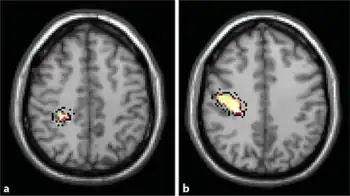

| Primary lateral sclerosis -a)Image shows abnormal hyperintensity in left subcorticol precentral region b) image shows reduced NAA peak and NAA:Cr ratio in the left brain hemisphere | |